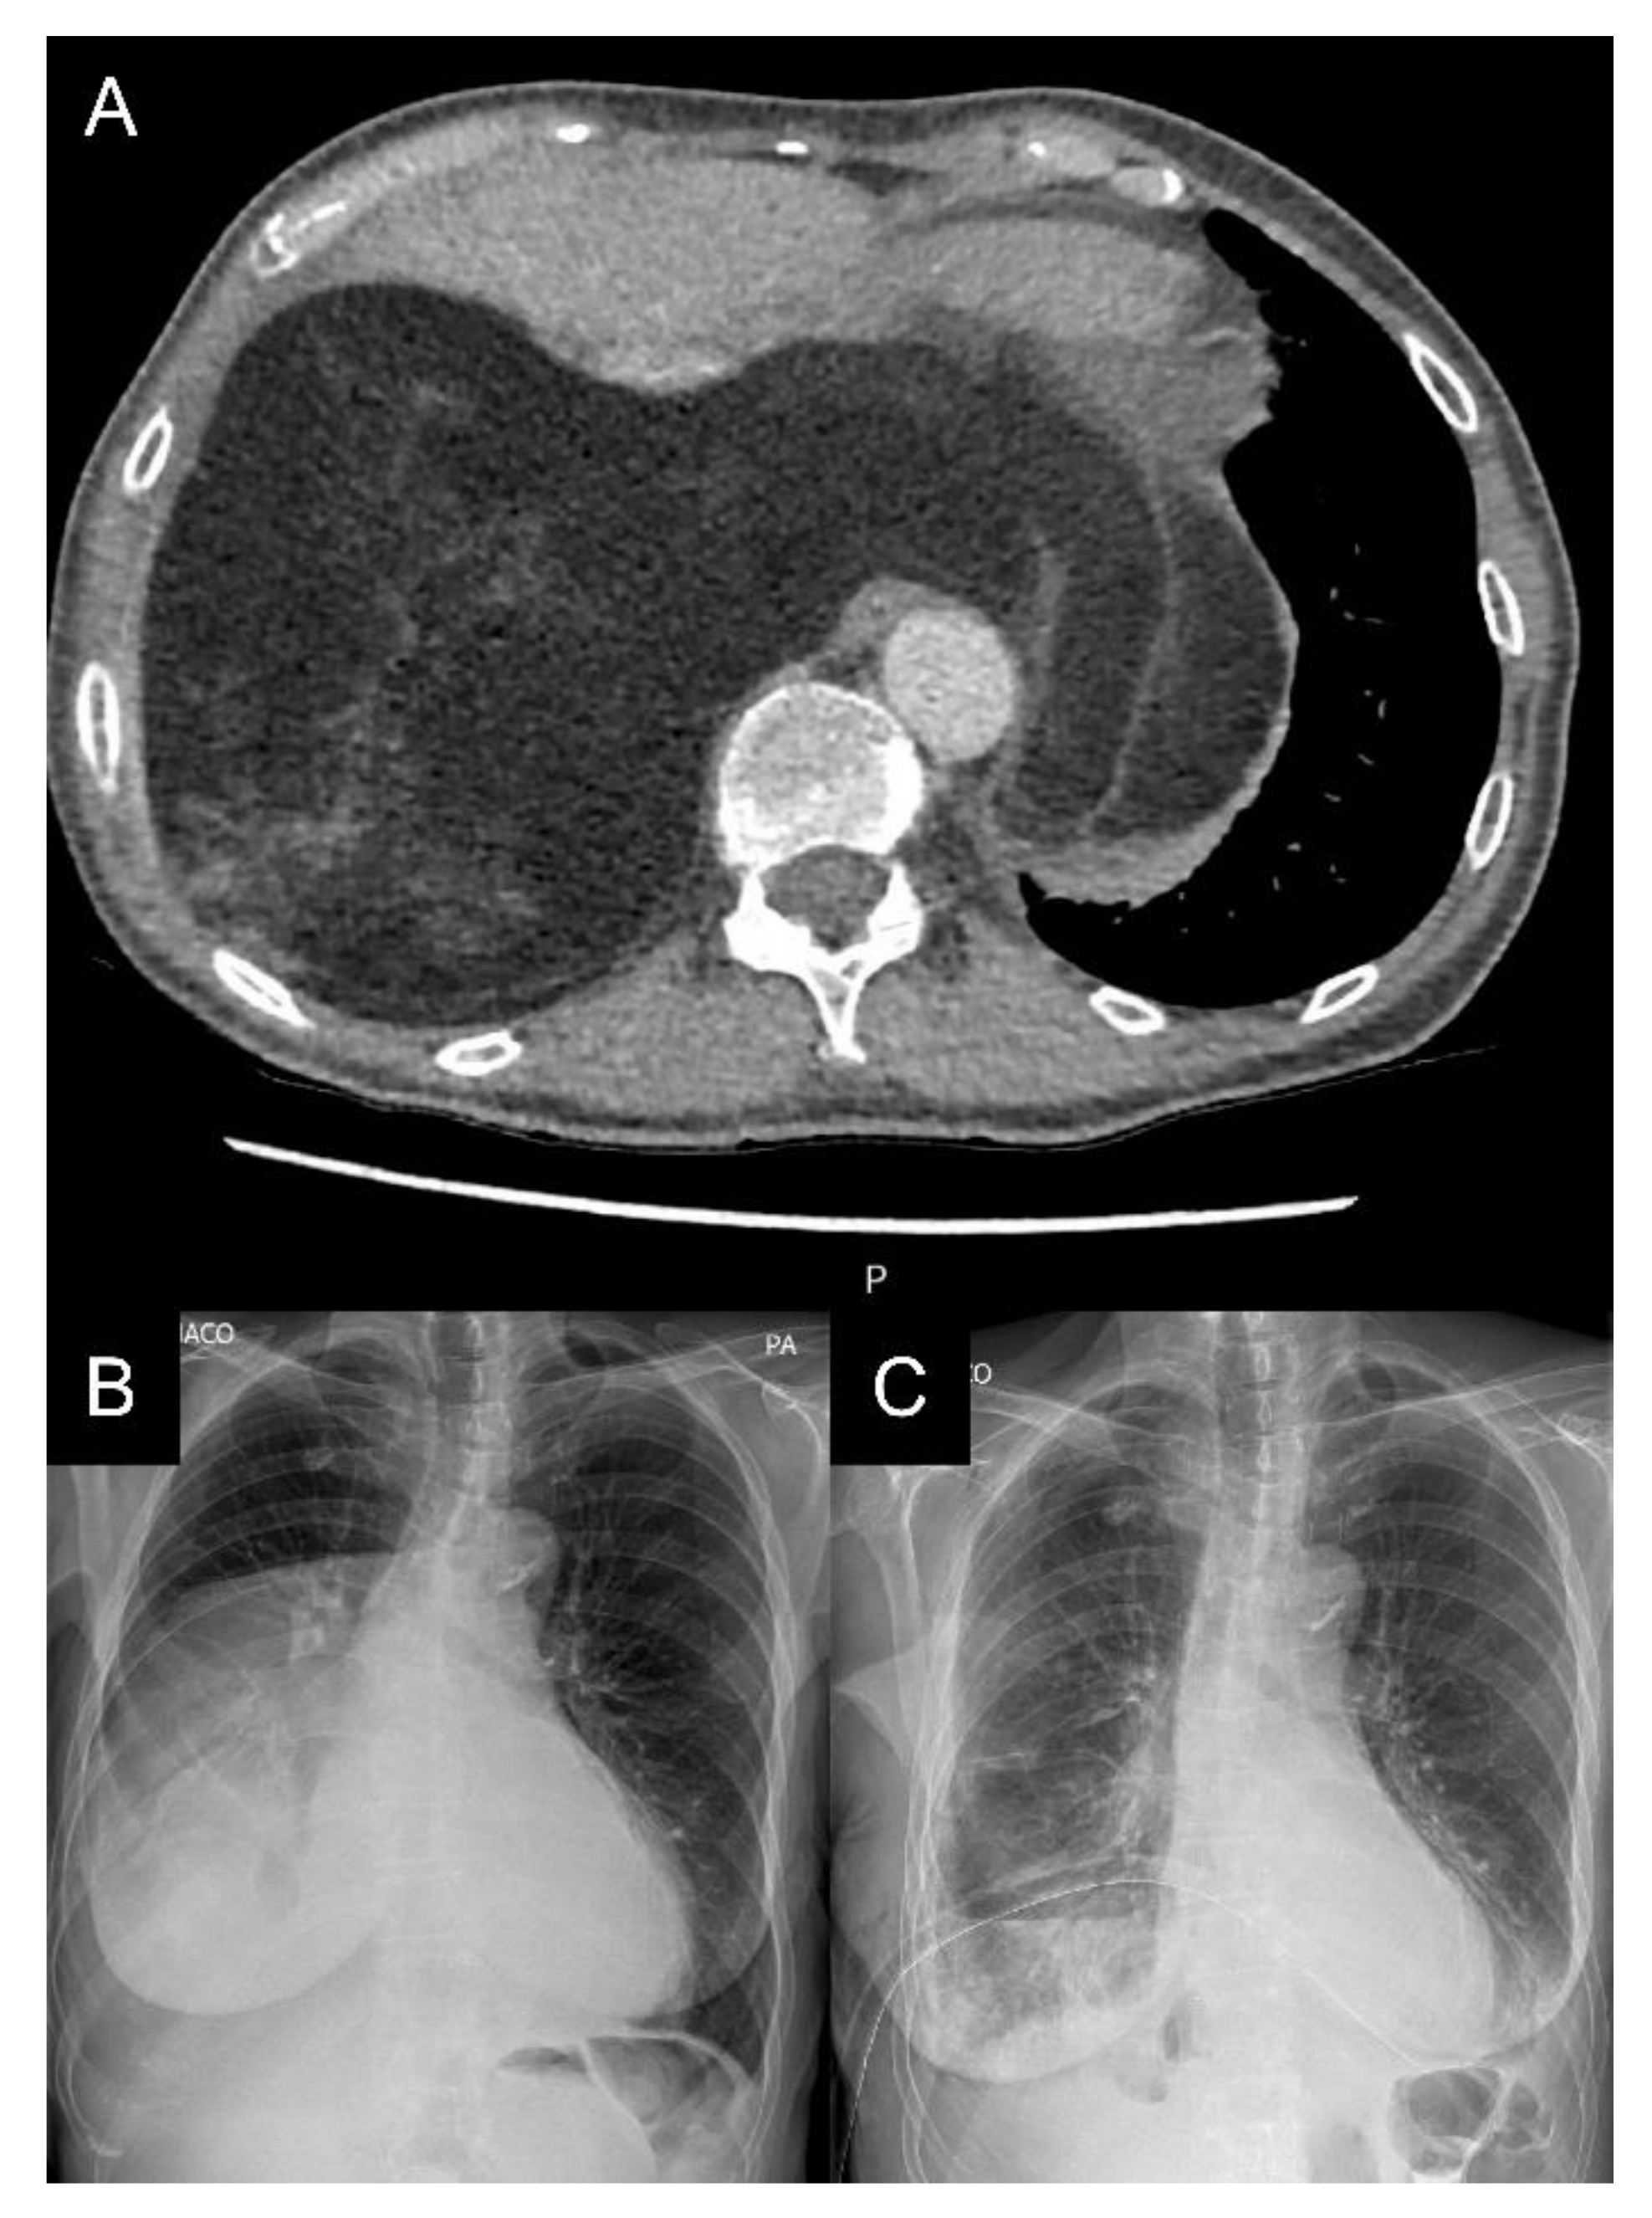

2. Case Report

5.2. Radiological Imaging